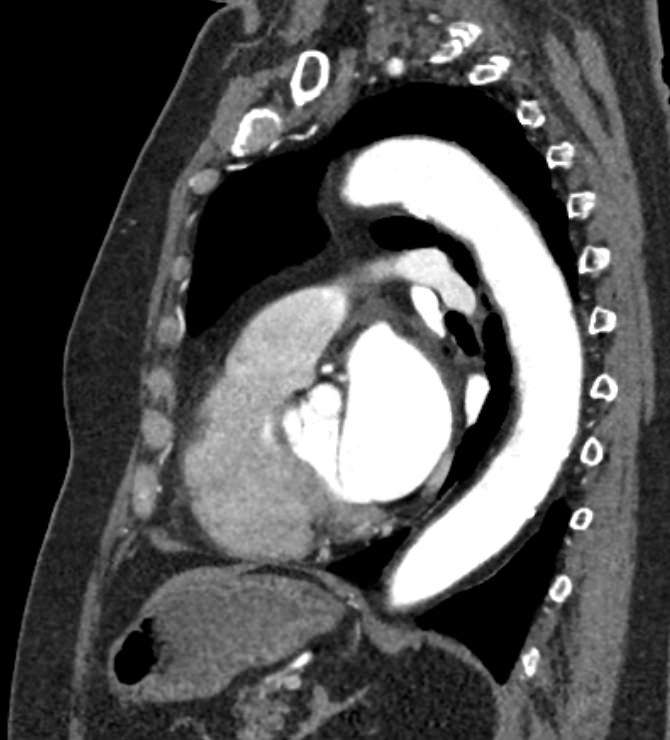

Грудная аорта делится на несколько отделов – восходящий отдел аорты, дуга аорты и нисходящий отдел. Корень аорты отходит непосредственно от левого желудочка, в его состав входят синусы Вальсальвы от которых берут начало коронарные артерии. После корня, прослеживается тубулярная часть восходящего отдела аорты, которая переходит в дугу аорты.

При истончении стенки аорты или ее ветвей формируется аневризматическое расширение участка сосуда, которое долгое время может никак себя не проявлять. Симптомы часто появляются при развитии осложнений – расслоения аневризмы (при разрыве внутренней оболочки сосуда и возникновения внутристеночной гематомы), разрыве аневризмы. Эти угрожающие жизни состояния можно избежать при своевременном выявлении аневризмы и проведения хирургического лечения.

Одним из информативных методов диагностики сосудистой патологии является мультиспиральная компьютерная томография грудной аорты и ее ветвей (КТ-ангиография). Метод сканирования при помощи рентгеновских лучей и цифровой обработки данных позволяет получать послойные снимки сосудов и трехмерные реконструкции сосудистой системы в мельчайших подробностях.

Для того, чтобы качественно визуализировать сосудистую систему КТ-ангиография предусматривает в обязательном порядке применение контрастного усиления. Йодсодержащее контрастное вещество вводится пациенту внутривенно и, благодаря способности контраста поглощать рентгеновские лучи, ярко контрастирует сосудистую систему на фоне окружающих тканей.

КТ-ангиография позволяет диагностировать аневризмы аорты, сосудистые аномалии развития, воспалительные изменения стенок сосудов, пристеночные тромбы, сужения просвета сосудов за счет сдавления извне близлежащими опухолевыми образованиями.